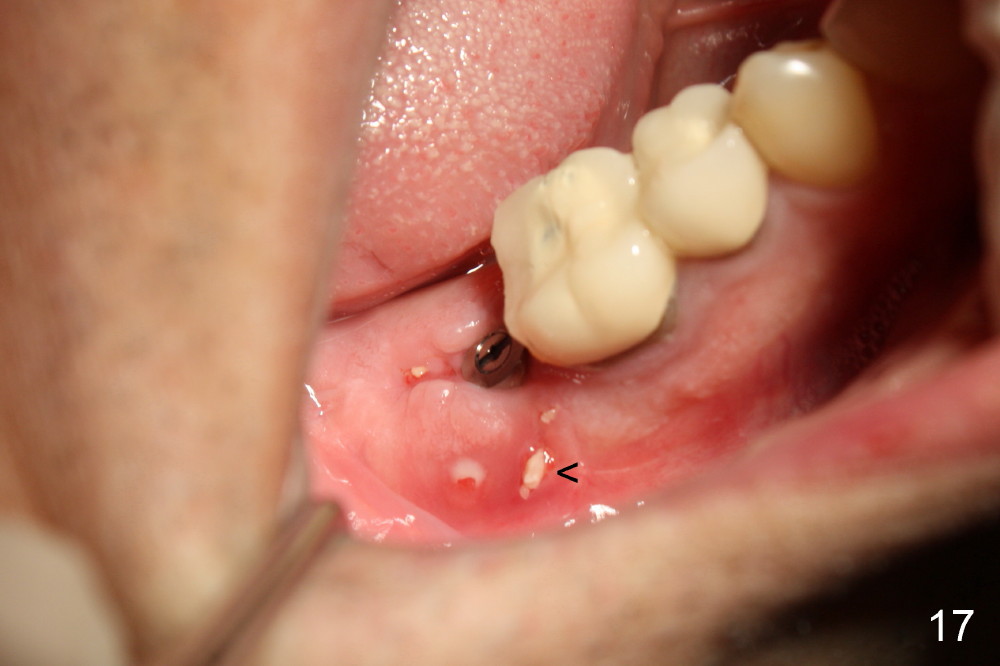

The flap is sutured to cover the gingiva-level implant for hemostasis. Fig.14 shows the wound 7 days postop. The implant is exposed 3 weeks postop (Fig.15).

Four months postop, there is a sign of osteointegration (Fig.16 <). Graft particles migrate to the surface of the mucosa (Fig.17 <). A healing cuff is placed over the implant for preparation of restoration (Fig.18 H); graft particles are removed (<). Due to insurance issue, the restoration is yet to finish by 6 months postop (Fig.19 C: healing cuff); the cystic lesion appears to have been decreased concentrically (*). The bone density in the former cyst area continues to increase 14 and 32 months postop (Fig.20 A: abutment; Fig.22). Small piece of bone graft (<) is being extruded distobuccal to the #31 crown (C) asymptomatically 15 and 32 months postop (Fig.21,22).